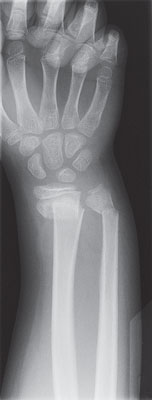

| Radiografía de una fractura de la muñeca. |